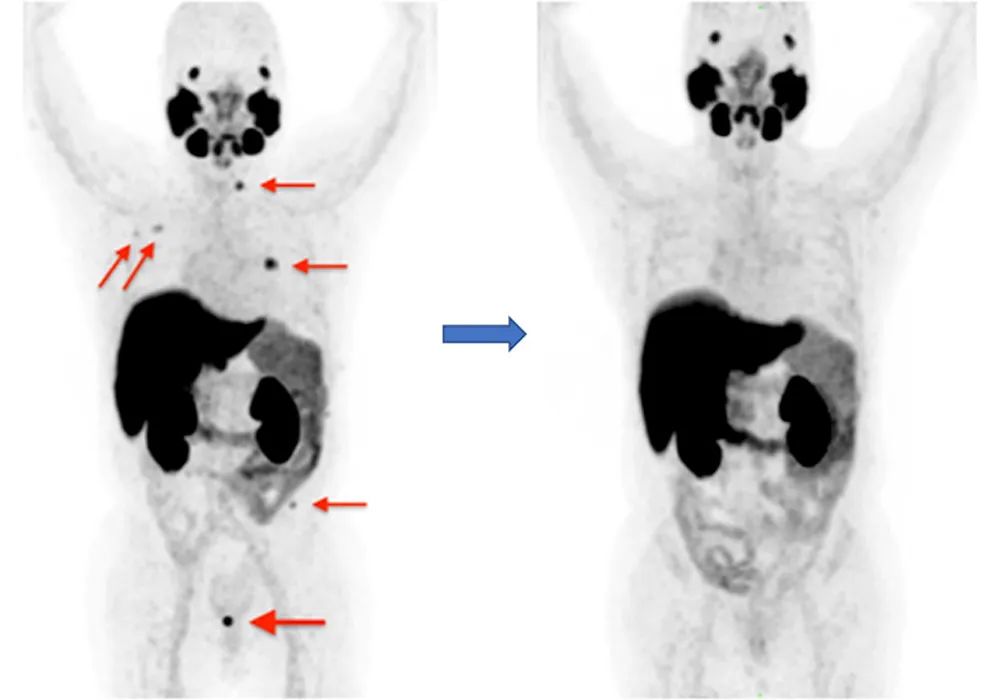

最大強度投影圖像顯示在盆腔中存在異常的F-18 PSMA-1007濃度,提示前列腺癌的局部復發(fā)(左,粗箭頭),預處理檢查中的局部骨轉移(左,細箭頭),以及它們在治療后(立體定向和雄激素剝奪治療)檢查中的不存在(右)。圖片由4.0國際許可證通過CC進行的診斷和介入成像研究提供。